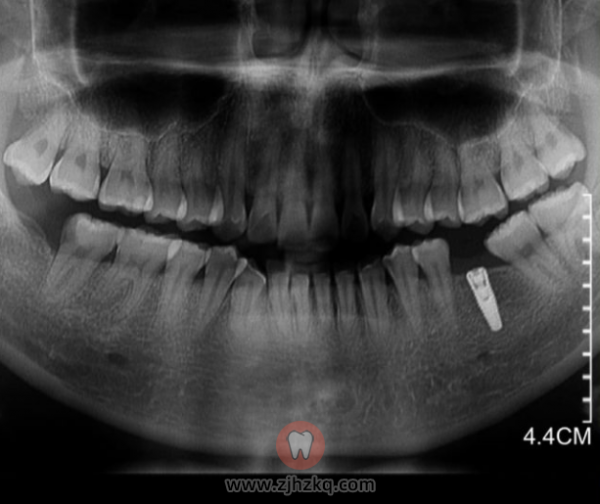

浙江**种植牙,种植一颗全瓷冠假牙,一共要去7次医院,最终总结:

1、总产生医疗费用:17564.97元(不需要洗牙、拔牙,治疗、骨量合适的情况)

自费部分:14061.55元

2、总耗时:3月24日–8月25日 (5个月1天)